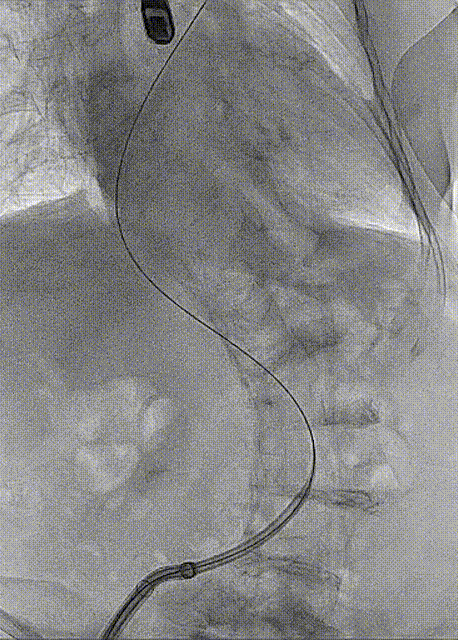

房间隔穿刺

手术过程